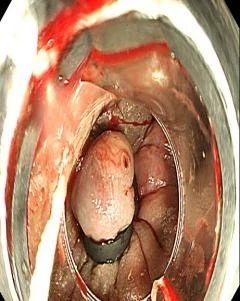

消化内科(kē)主任張排旗立即與其家屬溝通并征得(de)同意後,在手麻科(kē)的配合下行電子結腸鏡檢查,檢查中在肛門(mén)口可(kě)見(jiàn)脫出的内痔呈噴射狀出血,肉眼可(kě)見(jiàn)一柱狀血流不斷噴湧而出,情況危急。

在嘗試藥物注射止血效果不理(lǐ)想的情況下,張排旗果斷選用橡皮圈對出血痔核進行套紮,出血立即停止,患者安返病房(fáng)。次日(rì)查房(fáng)時,套紮的痔核因缺血變成紫黑(hēi)色,取得(de)比較好的内鏡下止血效果。